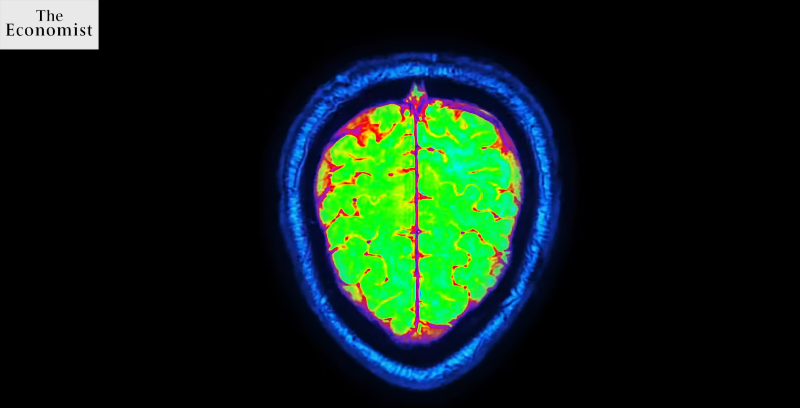

by Karolinska InstitutetSome of the researcher's PET-images.Roughly twenty years before the first symptoms of Alzheimer's disease appear, inflammatory changes in the brain can be seen, ac